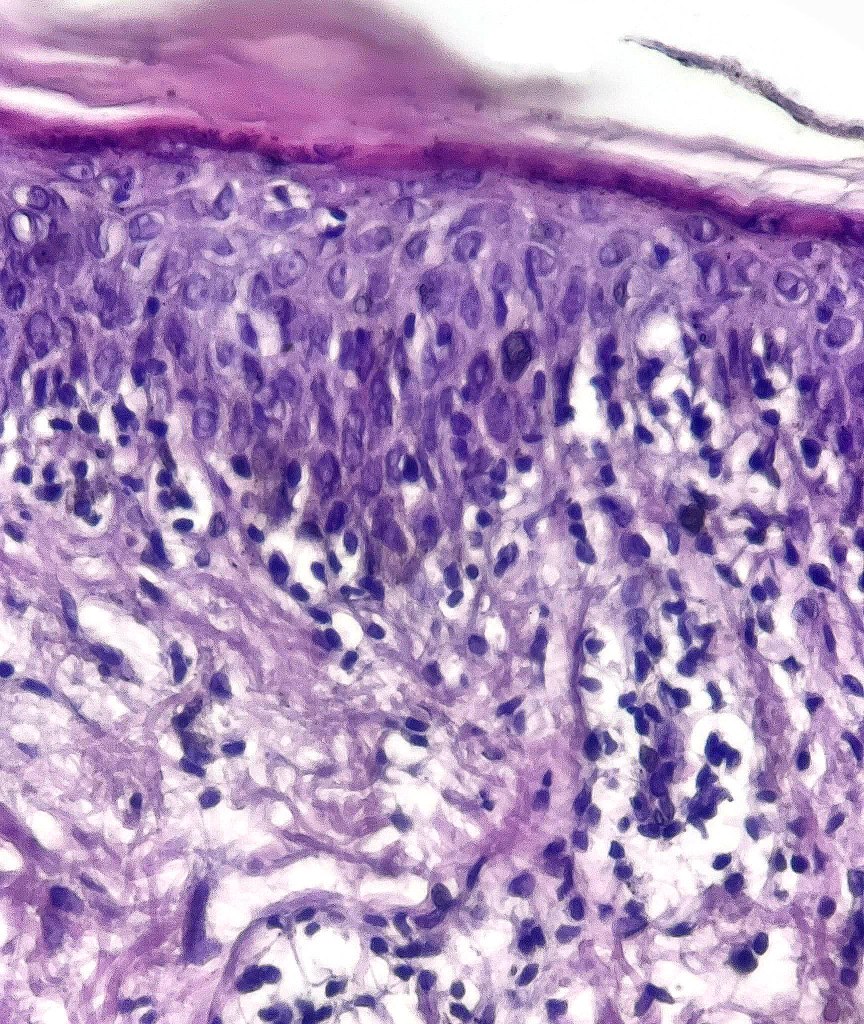

Histological features

•Indistinguishable from classical mycosis fungoides with the additional feature of marked pigmentary incontinence

•CD8+ve cells may predominate